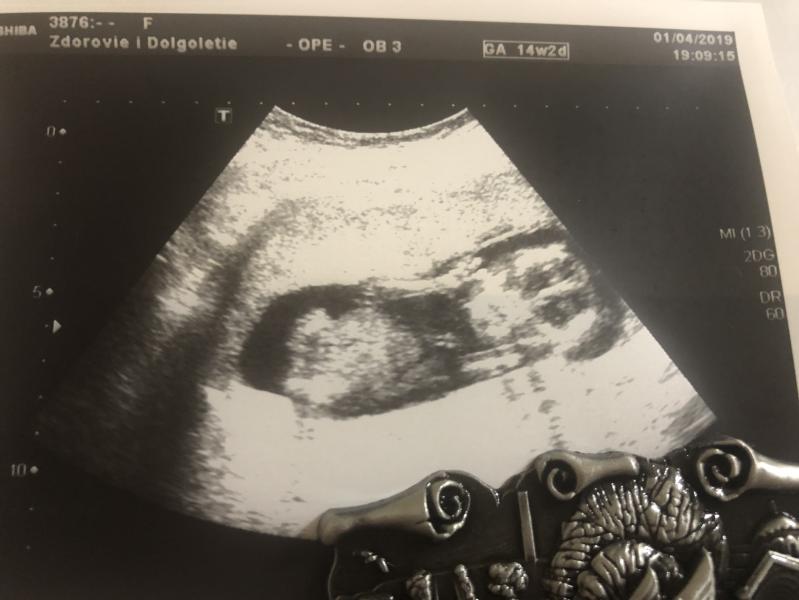

Сегодня была на УЗИ😊 У нас будет третий сынок🥰🥰🥰 Даже ручкой помахал, знакомился☺️